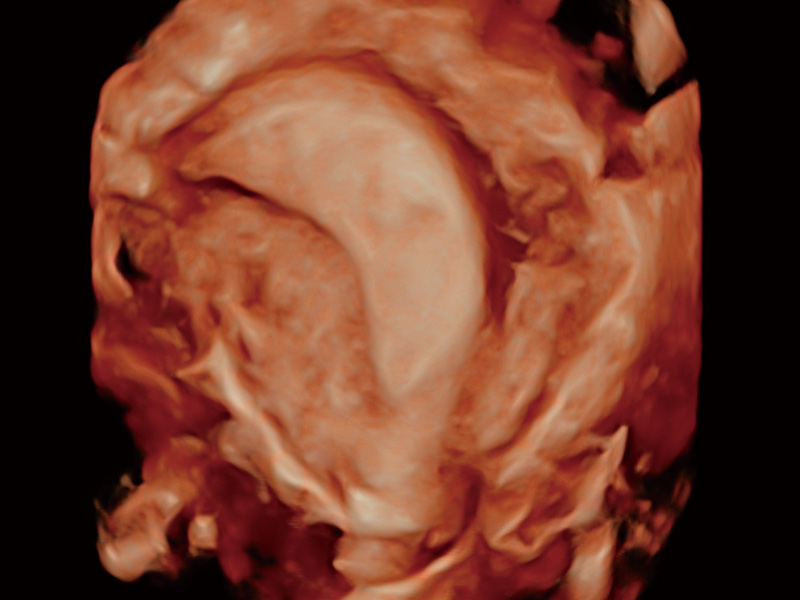

单角子宫

子宫内膜息肉